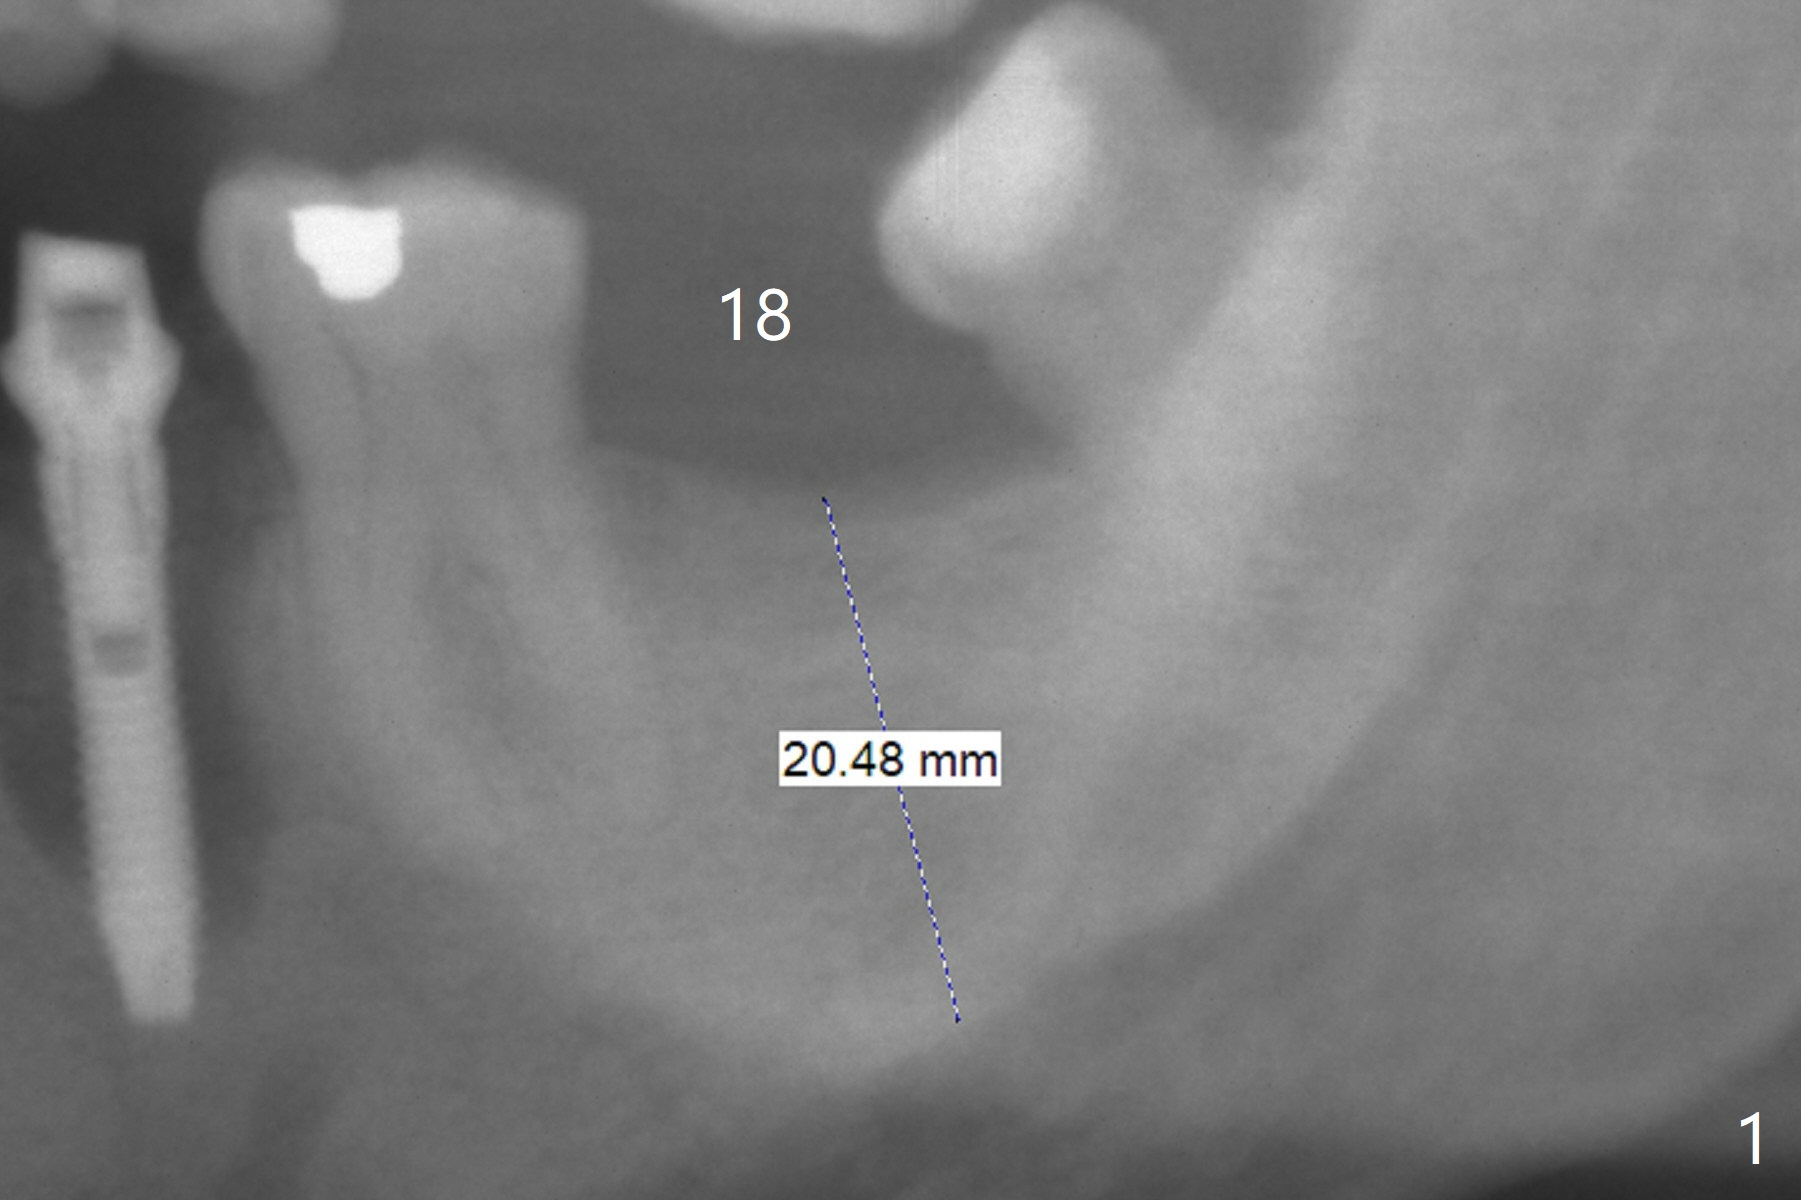

It is difficult to identify the Inferior Alveolar Canal when the initial osteotomy depth is 11.5 mm (Fig.2). Following sequential osteotomy (last drills 4.5x11.5 and 4x13 mm), a 5x11.5 mm implant is placed with >50 Ncm (Fig.3,4). Later the implant is placed .5 mm deeper with placement of a 6.5x4(4) mm abutment and autogenous bone lingually, in which ~.5 mm implant is uncovered. There is mild bone loss distal 6.5 months postop (Fig.5). Before cementation, the crown at #29 becomes loose. The abutment screw needs retightening 6 months post cementation. Six months post retightening, the abutment screw is loose at #14.